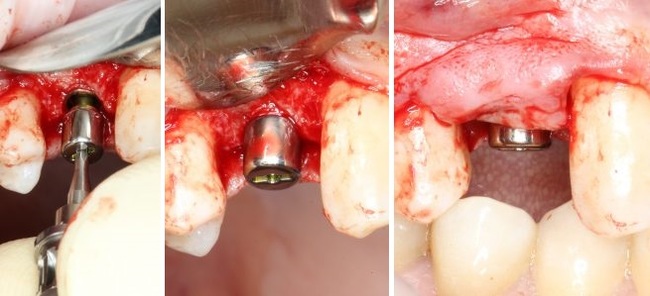

Следующий этап - установка формирователя десны

С учётом клинических условий, мы подобрали к установленному мплантату формирователь Slim (без расширений) высотой 3 мм:

Заканчиваем нашу операцию наложением швов

И контрольным снимком